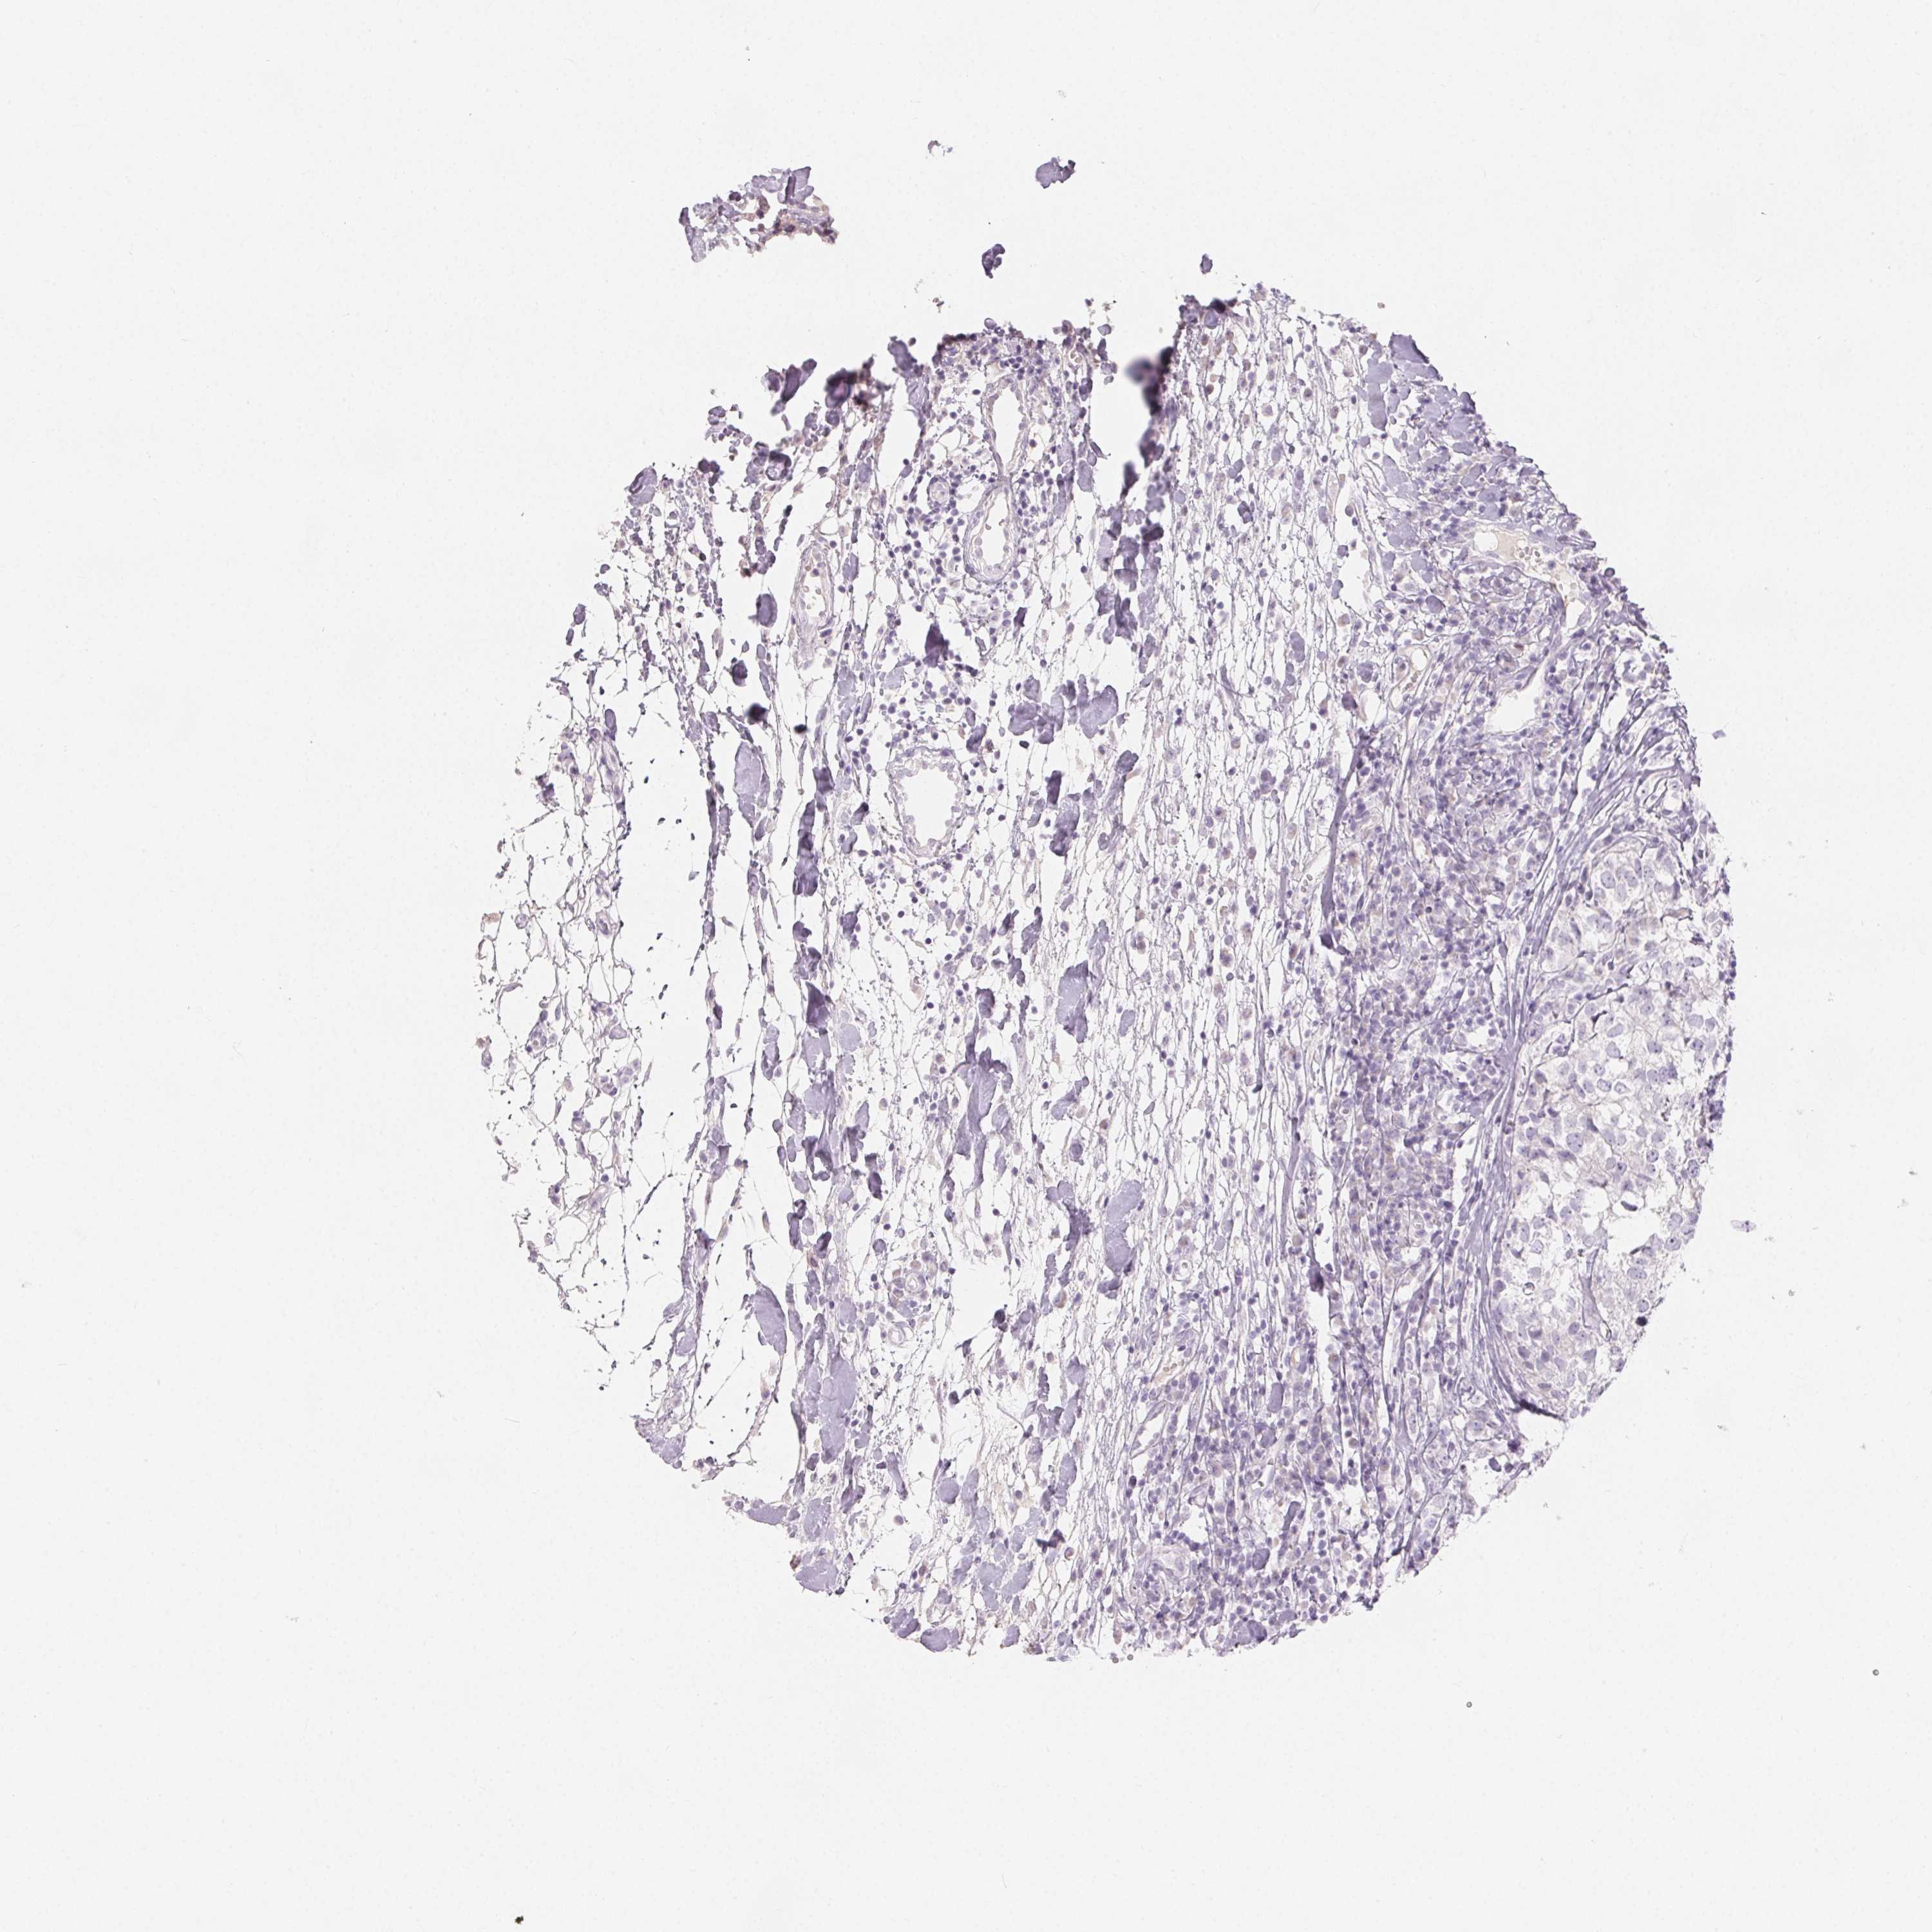

CANCER BREAST CANCER Show tissue menu

BRCA TCGA BRCA VALIDATION PROTEIN EXPRESSION

MIOX is not prognostic in Breast Invasive Carcinoma (TCGA)